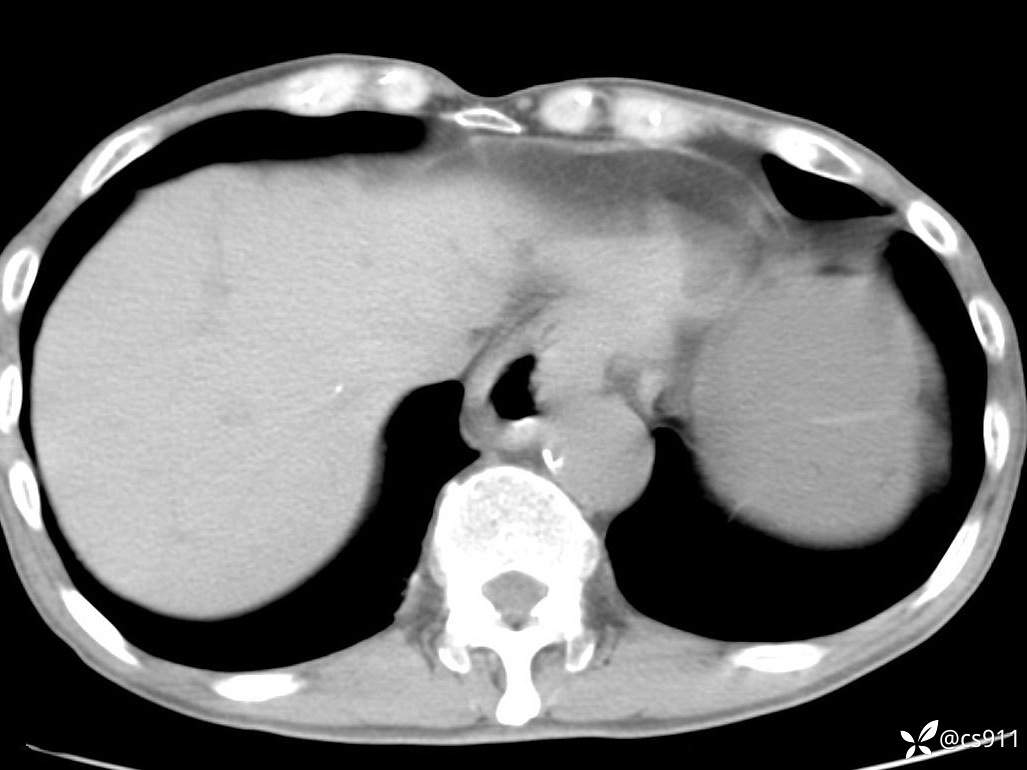

急腹症之急诊CT,原因?答案公布

男,77岁,腹痛、腹胀伴恶心呕吐1天。呕吐胃内容物,非喷射性呕吐,有咖啡色样胃内容物,诉有胃穿孔病史。查体:全腹平,下腹部压痛,全腹无反跳痛,叩诊呈浊音,移动性浊音阴性,肠鸣音减弱,1-2次/分。肛检:直肠未扪及明显肿物,可触及大量粪块。

血淀粉酶(AMY) HH 1859 U/L 35-135